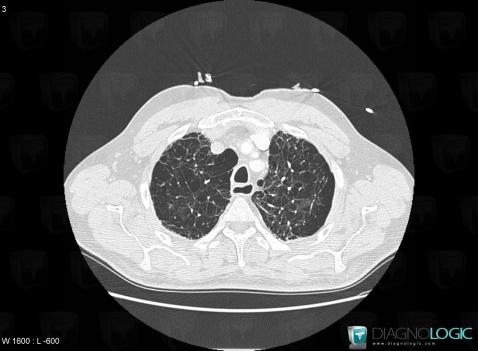

Centrilobular emphysema, Pulmonary parenchyma, CT

Here is the specific information in the key image above:

- Diagnosis Centrilobular emphysema (link to Emphysema), Location(s) Pulmonary parenchyma, with gamuts Multiple cystic lung lesions